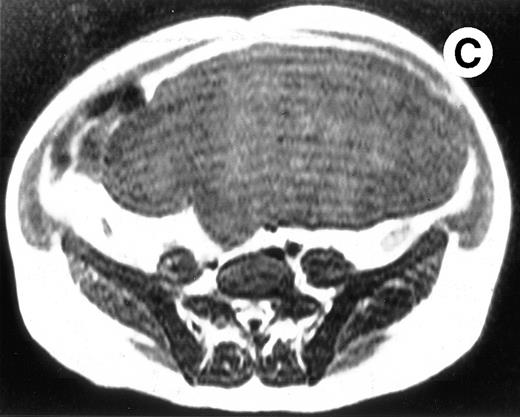

Surgical pathology showed a 6.5-kg spleen with nodular appearing external surfaces and focal subcapsular infarcts, ranging in size from 0.5 to 3.4 cm. Serial sections showed rubbery and focally fibrotic surfaces (Fig 2A). This correlated with his presurgical axial T2-weighted MRI, which demonstrated multiple low signal intensity nodules not seen on T1-weighted views (Fig 2B through D). Although MRI is useful in monitoring response to therapy, this case demonstrates that volumetric measurements alone may not be adequate, especially when there are multiple areas of decreased signal intensity on T2-weighted STIR images. Both splenic nodules and infarcts are common in Gaucher patients, occuring in approximately 30% and 32% of patients, respectively.5 Thus, the volume free of nodules and infarct may be a more reliable measure of response to enzyme therapy in these patients.

(A) Photograph of the patient's spleen showing multiple nodules (arrows) with area of subcapsular infarcts (curved arrows). (B) Coronal STIR MR image of the (L) liver and spleen (IR 2450/100/30) shows multiple low signal intensities nodules (curved arrows) in the enlarged spleen. (C) Axial T1-weighted (SE 300/10) MR image shows splenomegaly with no focal splenic signal abnormality. (D) Axial T2-weighted (SE 4293/80) MR image of the spleen at the same level as (C) shows multiple low signal intensity nodules in the enlarged spleen (arrows).